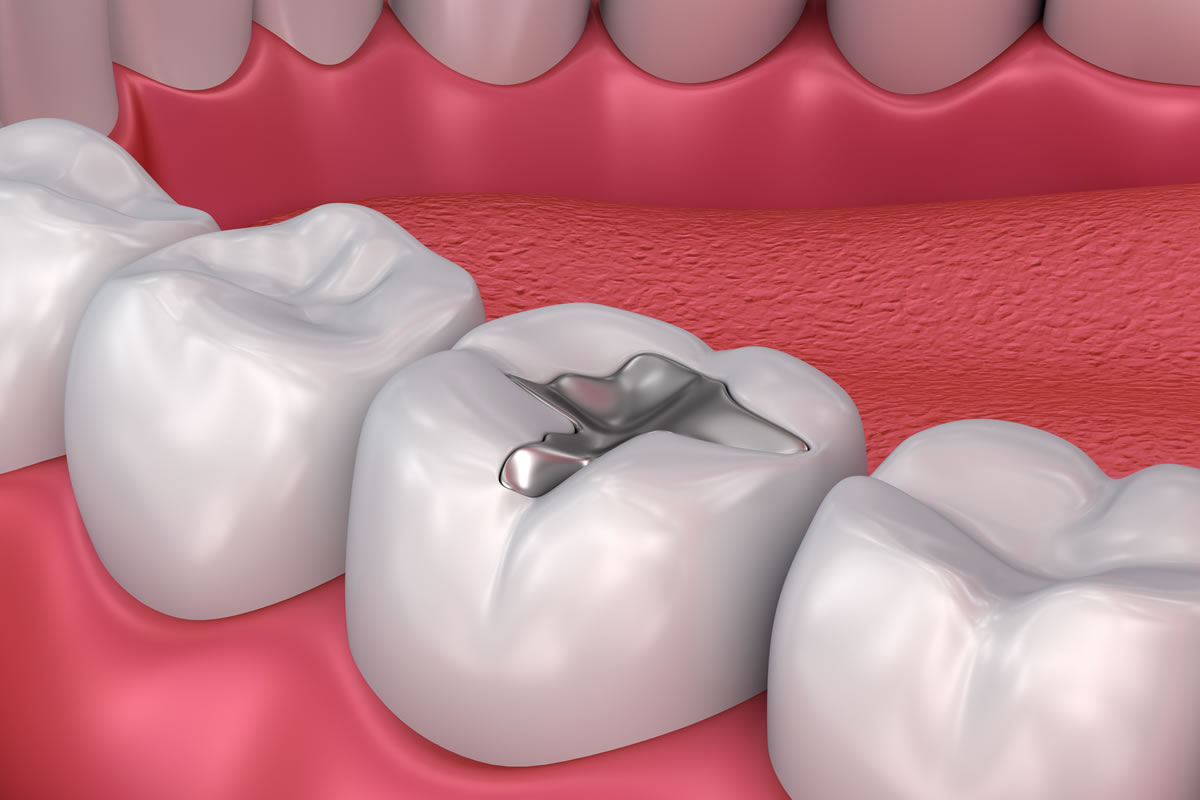

Fillings: Restoring Your Teeth to Optimal Health

Our fillings are designed to restore your teeth to optimal health, function, and appearance. Whether caused by decay, minor fractures, or wear, damaged teeth can compromise your oral health if left untreated. Using high-quality, tooth-colored materials, we carefully remove the affected areas and fill the space to prevent further damage while blending seamlessly with your natural teeth. Our precise techniques ensure a comfortable experience and long-lasting results. With our expert care, you can trust that your smile will be both healthy and aesthetically pleasing.